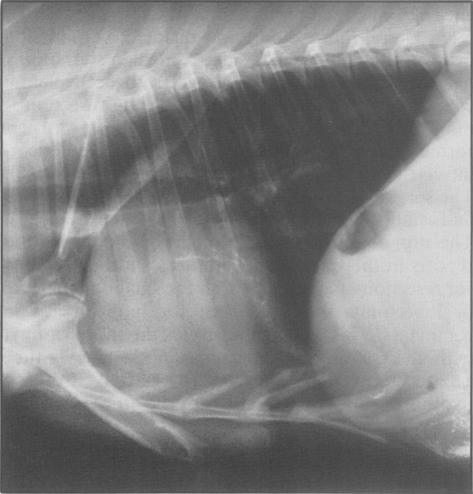

Resolution of pyothorax in a deer by a thoracotomy, drainage and lavage via tube thoracostomy.